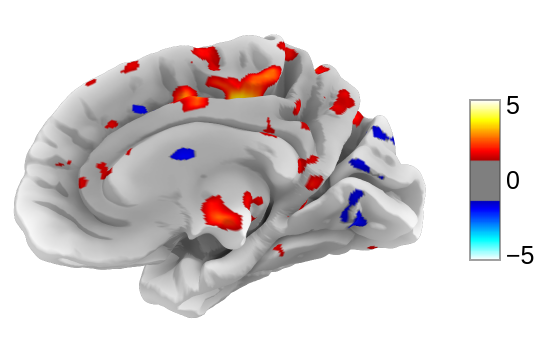

7.6. Surface plotting¶

Plotting functions required to plot surface data or statistical maps on a brain surface.

Added in version 0.3.

|